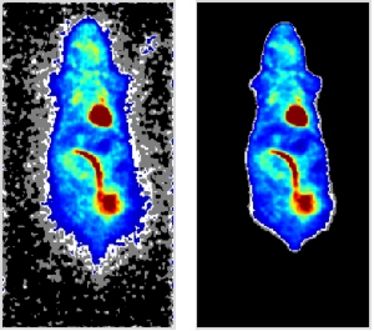

1. Small Animal Imaging Workshop in Münster

1. Small Animal Imaging Workshop in Münster

22.11.2010

- 26.11.2010

1. Small Animal Imaging Workshop in Münster

1. Small Animal Imaging Workshop in Münster

22.11.2010

- 26.11.2010

1. Small Animal Imaging Workshop in Münster

1. Small Animal Imaging Workshop in Münster